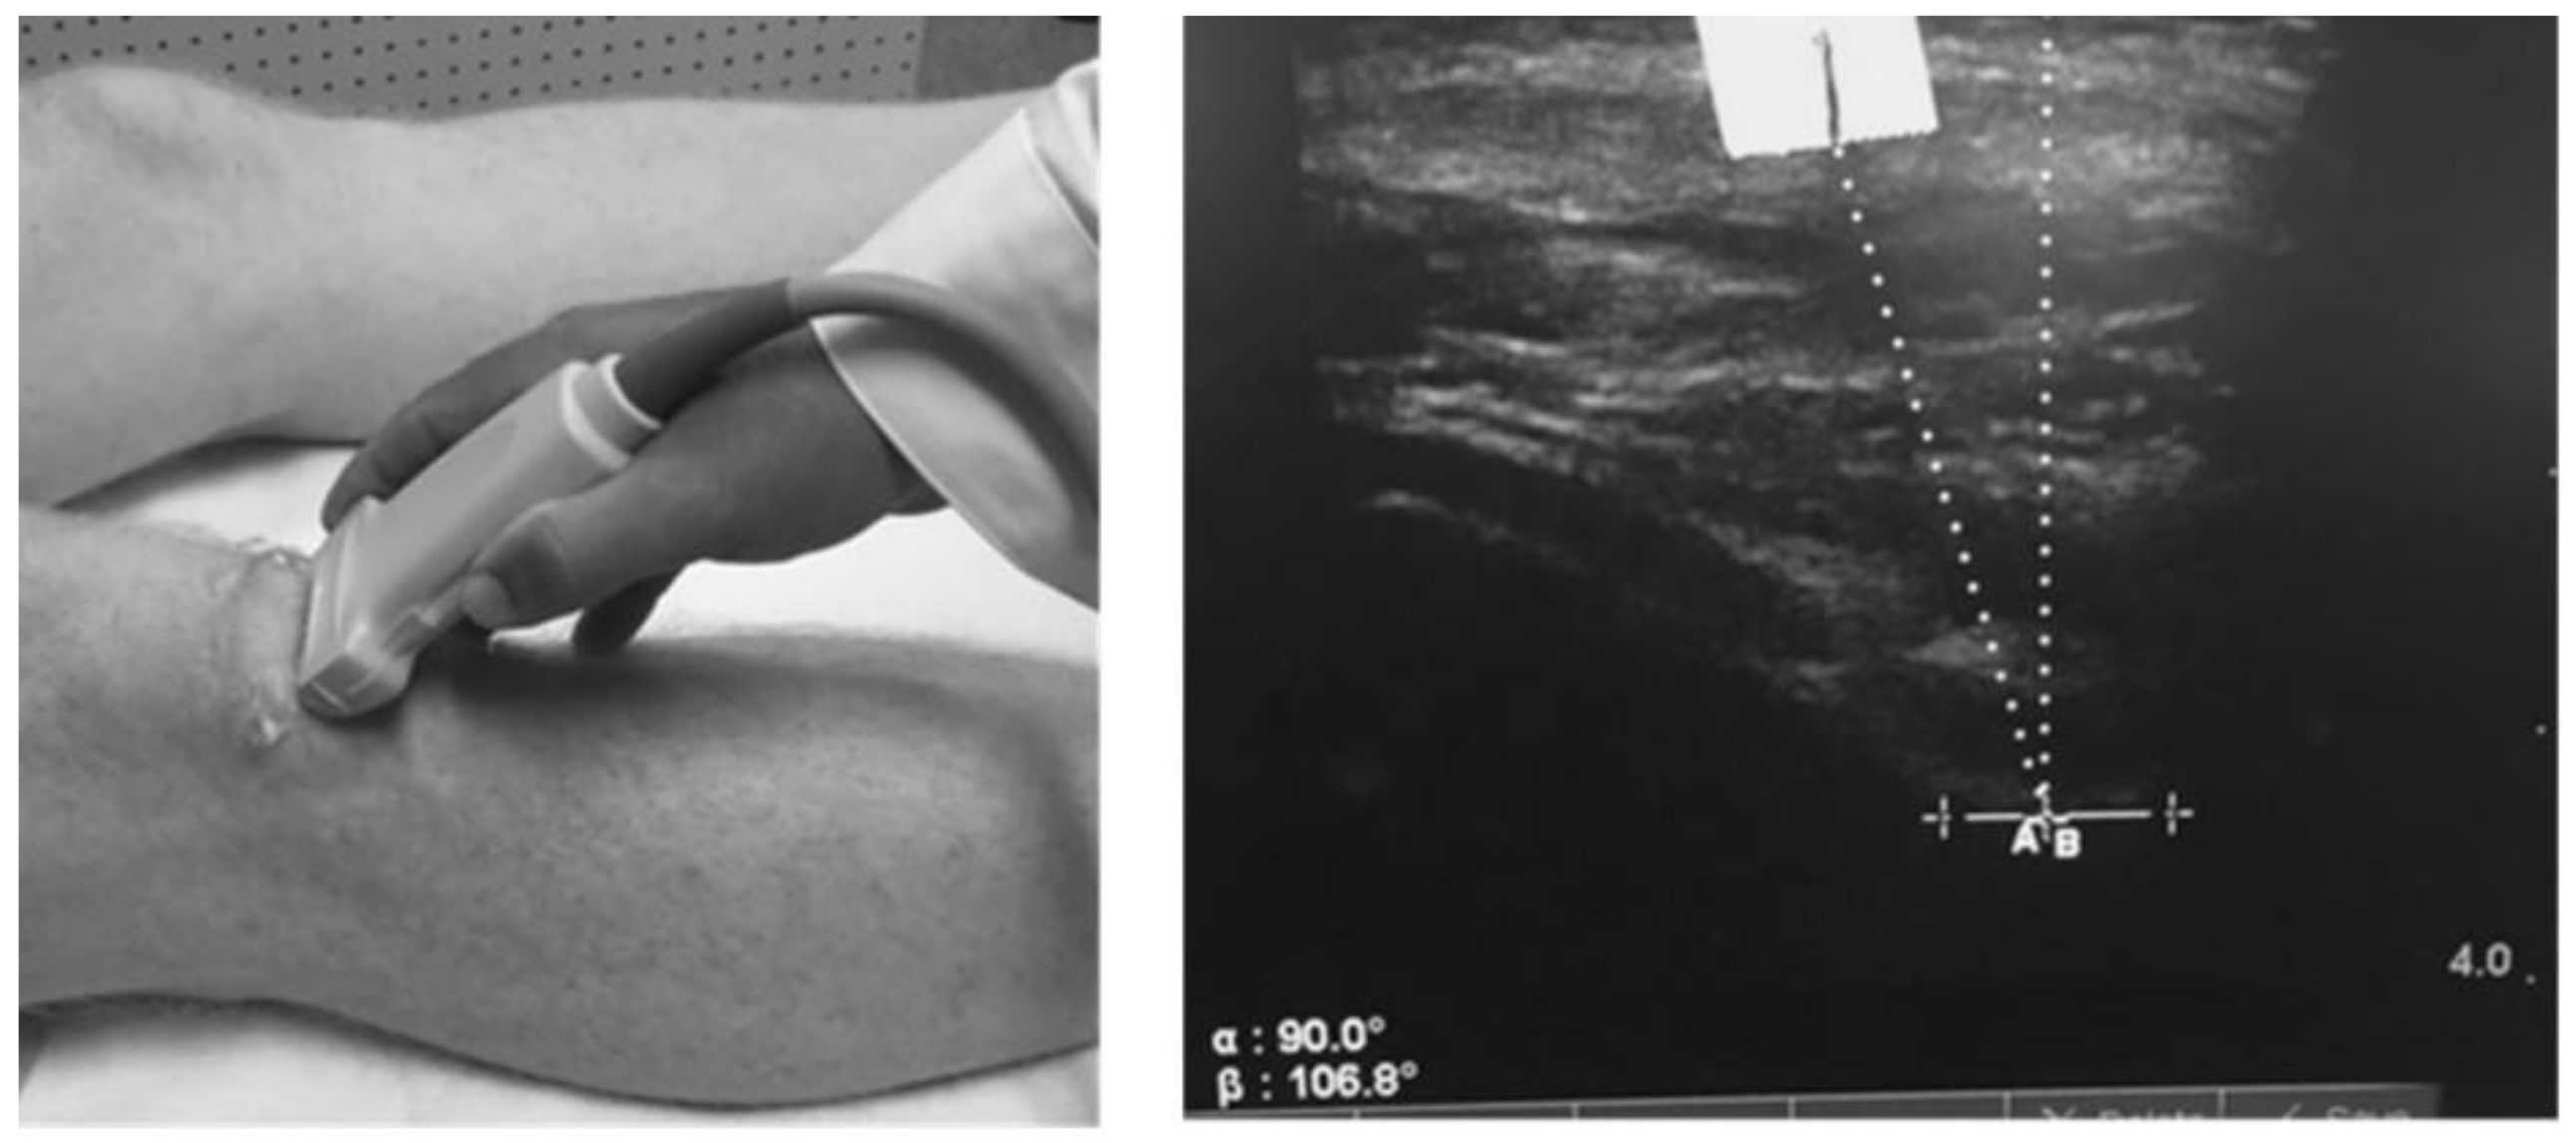

2.4. Static Patella Position

- Anillo, R.; Villanueva, E.; León, D.; Pena, A. Ultrasound diagnosis for preventing knee injuries in Cuban high-performance athletes. MEDICC Rev. 2009, 11, 21–28. [Google Scholar] [PubMed]